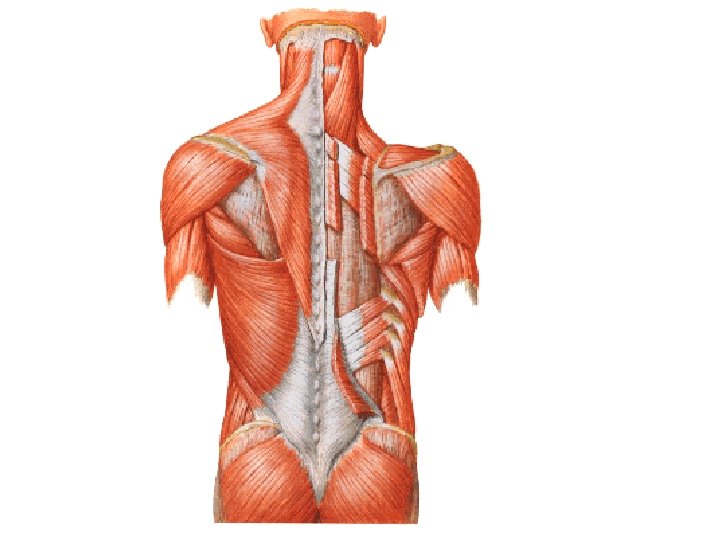

M. supraspinatus M. infraspinatus M. teres minor M. teres major M. subscapularis

N. suprascapularis N. axillaris

ARTERIAL ANASTOMOSES AROUND THE SCAPULA A. transversa colli A. suprascapularis A. circumflexa scapulae A. circumflexa humeri post.

Rotator cuff